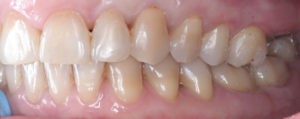

Искривление окклюзионной кривой (плоскости смыкания зубов), возникшее в результате парадонтита, успешно удалось устранить, используя накусочные брекеты на верхних резцах и микроимплант, установленный во фронтальном участке нижней челюсти:

Для предварительной подготовки были привлечены пародонтолог и ортопед, поскольку отсутствие нескольких зубов, заболевание пародонта и дефекты твердых тканей зубов сопутствовали основной патологии. Проведены пародонтологические процедуры, вылечен кариес и его осложнения, изготовлены временные коронки для зубов с большим разрушением. На фото — временные коронки на боковых зубах.